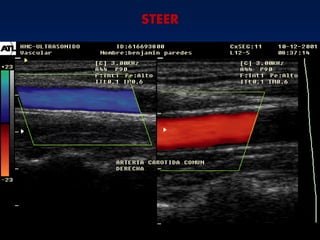

STEER

STEER: Es el área

del

Cuadrado donde se

Valora la muestra

Interpretacion del Flujoen el Doppler en color Flujo Haciaeltraductor Nohaycambiode frecuenciaDoppler Alejándose deltrasductor Color Rojo-naranja/amarillo Negro Azul-azulclaro/verde

Flujo laminar delos vasos Velocidades Máximas en el centro Velocidades Mínimas en el extremos

Velocidad de flujoen la periferia del vaso STEER: Es el área del Cuadrado donde se Valora la muestra Volumen de la muestra